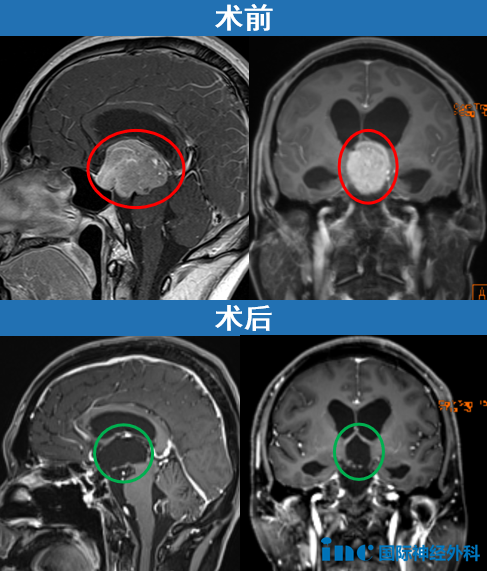

一位62岁女性患者,与垂体瘤抗争已达35年,曾因垂体瘤复发接受放射治疗。本次因复视症状随访检查,发现已发展为巨大垂体瘤。实施开颅手术后,术后影像显示肿瘤切除彻底。

Couldwell教授演讲中展示部分巨大垂体瘤病例。目前巨大垂体瘤主要治疗方式为手术,目的在于最大程度切除肿瘤、改善神经功能障碍以及保留正常垂体功能。巨大垂体腺瘤术前根据影像学表现和临床症状,个体化选择合适手术入路,是成功切除肿瘤的关键。经蝶入路、经颅入路和联合入路是切除肿瘤的可行方法。